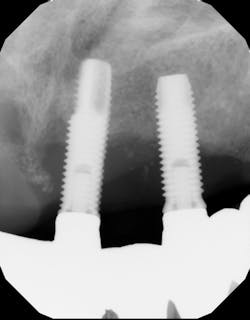

A recent retrospective study with a 10-year follow-up evaluated the long-term survival rates of natural teeth versus dental implants in 58 patients who were treated for chronic periodontal disease and then enrolled in periodontal maintenance programs.6 The study found that over 10 years, overall natural tooth loss (due to caries, endodontic reasons, and/or periodontal reasons) was .07 teeth per patient per year and .04 teeth per patient per year for periodontal reasons.

On the other hand, dental implant loss was 10 times higher, at .4 implants lost per patient per year. Ninety percent of the periodontally compromised teeth treated with active periodontal therapy (i.e., scaling/root planing, surgery, periodontal maintenance) survived over the 10-year period of the study. In addition, teeth designated with questionable prognoses at the baseline decreased by 1.9%, while teeth assigned with good prognoses increased by 3.6%. Overall implant survival in this study population was 90%, with 100% of implants surviving up to five years and then failing at a rate of 10.08% in the six- to 10-year range.

Another interesting finding in the study was that over the 10-year follow-up period, implants with a probing depth of six or greater and bone loss of 50% or greater increased 13.5% and 3.1%, respectively, while natural teeth decreased 8% and 10.7%, respectively. This would suggest that tooth prognosis increased over the study period, while implant prognosis decreased. Additionally, patients with probing depths of five or greater and/or full-mouth bleeding scores 25% or greater were at a significant increased risk for peri-implant disease, stressing the importance of controlling periodontal disease in patients who are candidates for implant therapy.8

Historically it was thought that in a patient with periodontal disease, once teeth were removed and implant therapy initiated, the pathogens that caused periodontal tooth loss would be eliminated and therefore not affect the dental implant.10 More recent literature has suggested that this is inaccurate, and patients with either chronic or aggressive periodontal disease may suffer from more biological complications with implant therapy.11

One implication of this article would be that once periodontally compromised teeth are extracted, dental implant surfaces can become colonized with potentially disease-causing periodontal pathogens without adequate biofilm control in the overall oral environment. This would apply even in full-mouth extraction cases with immediate or delayed implant therapy.